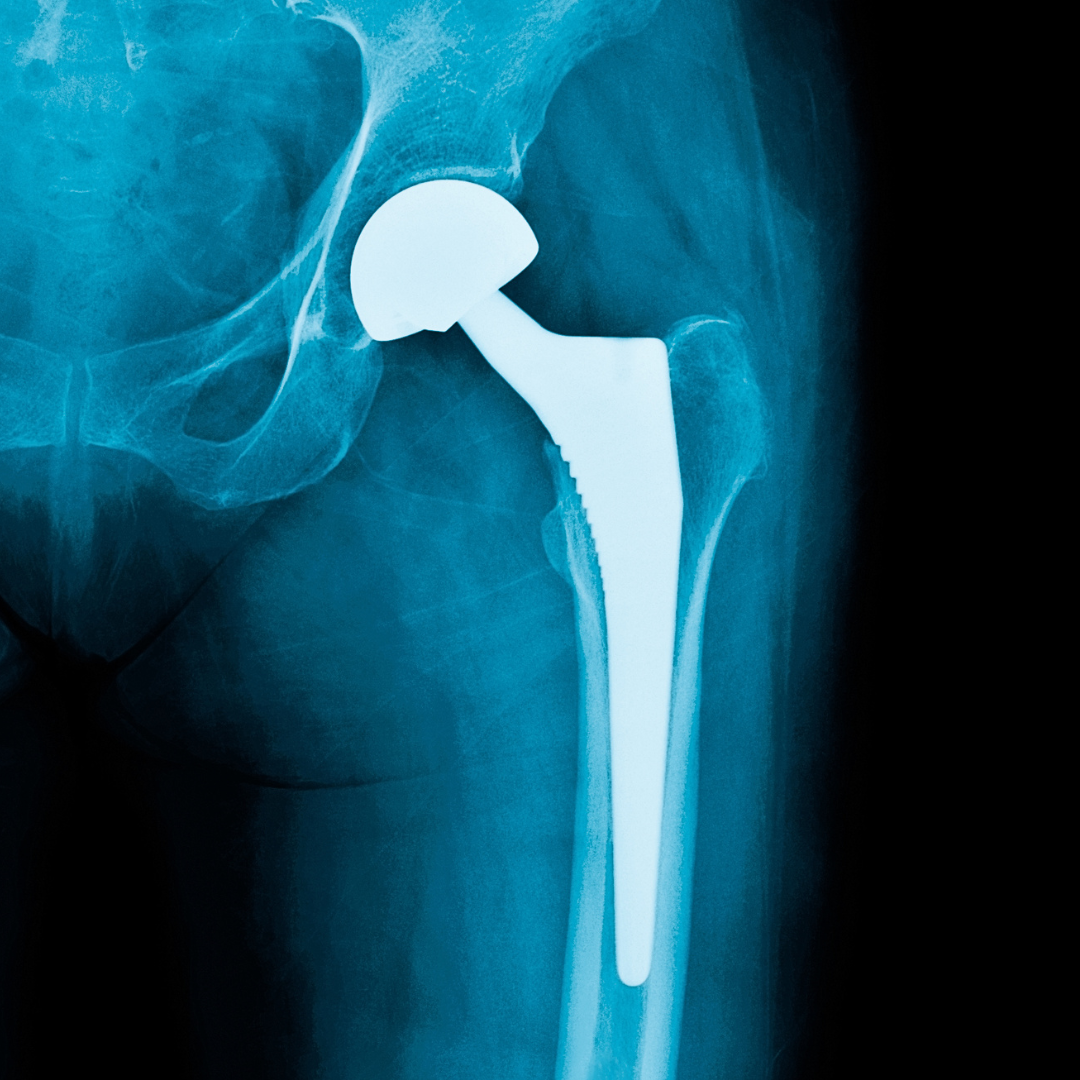

• X-ray Imaging: X-rays can show arthritis, joint space narrowing, bone damage, deformities, or fractures. This shows how much cartilage has been lost and how the structure of the hip joint has changed.

When the hip joint is very damaged and makes it hard to move normally, Hip Replacement surgery in Jaipur is done. The goal of surgery is to take out the worn-out joint surfaces and put in new ones that are stronger and allow for smoother, more stable movement. During the Process:

• The damaged femoral head (the ball of the hip joint) is carefully taken out.

• The hip socket is cleaned and ready for the artificial liner to be put in.

• A smooth metal stem with an artificial ball is put inside the thigh bone.

• A strong socket part is attached to the pelvic bone to put the joints back in their proper place.